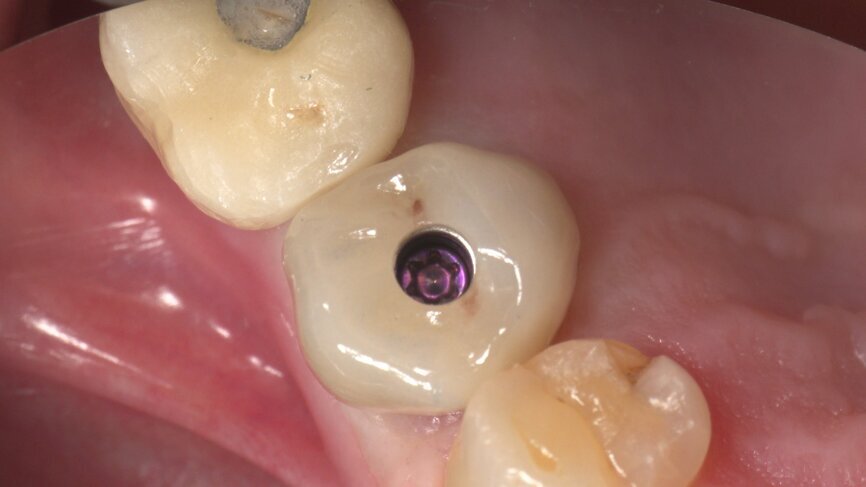

Returning to the patient, the healing caps were removed, and the crowns were placed. The occlusion was checked and contacts were inspected (Figs. 40–43). Screw holes were sealed with PTFE and a temporary filling material.

Once the crown was ready, the selected Variobase was cemented in the correct orientation in relation to the crowns. The crowns were stained and polished manually, and the whole process was finished about 1 hour after scanning (Figs. 36–39).